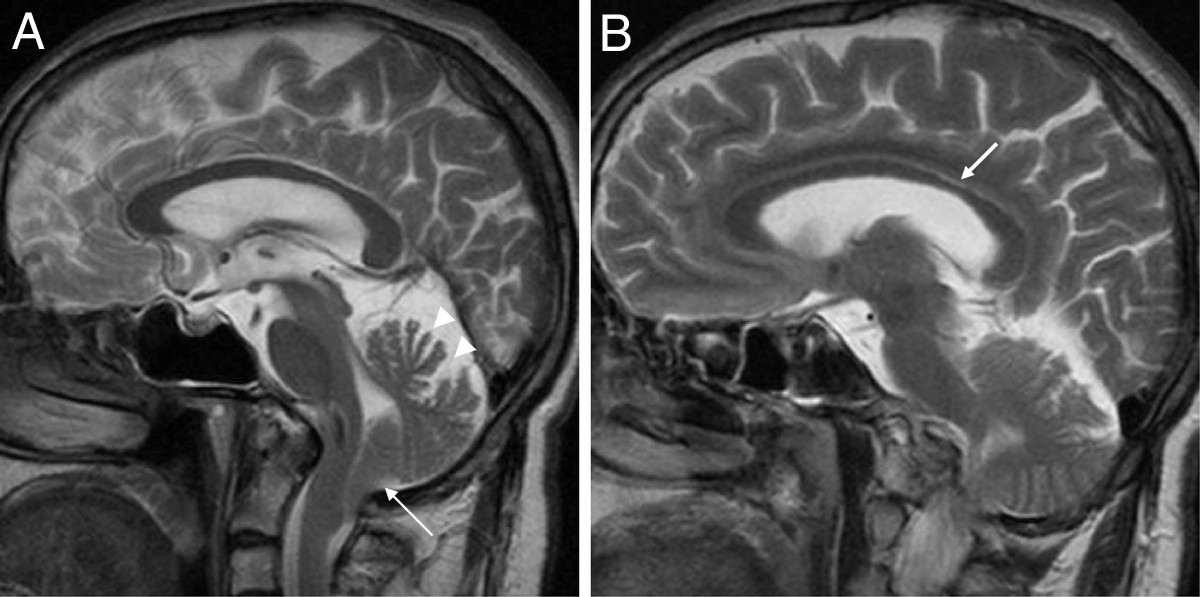

Аномалия Арнольда-Киари: MRI снимки